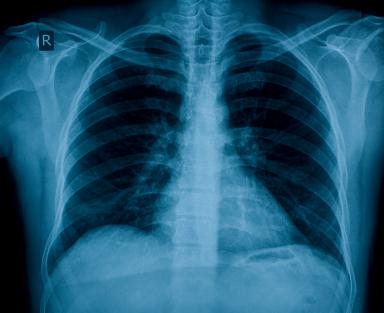

There are many reasons for wrong, mistaken or missed diagnosis. Some of them are: rushed doctors, unqualified doctors, poor communication with the patient, failure on the part of the doctor to research the symptoms or condition, misreading an ex–ray, mammography, ultrasound, or misreading a biopsy, misreading blood, urine or pap smear tests, misreading ex–rays, MRI’s or other images, and failure to eliminate all possible conditions corresponding to the symptoms.